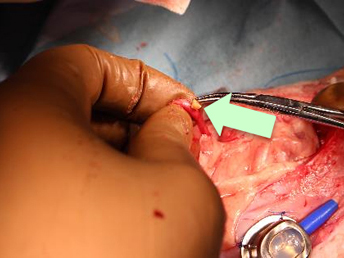

強い痛みが残る可能性もあるため、当院では尿管結石も除去しています。

尿管結石を全て取り除くため、尿管の再建手術が必要になりました。

尿管をつなぎ合わせました。髪の毛より細い糸でつなぎ合わせます。